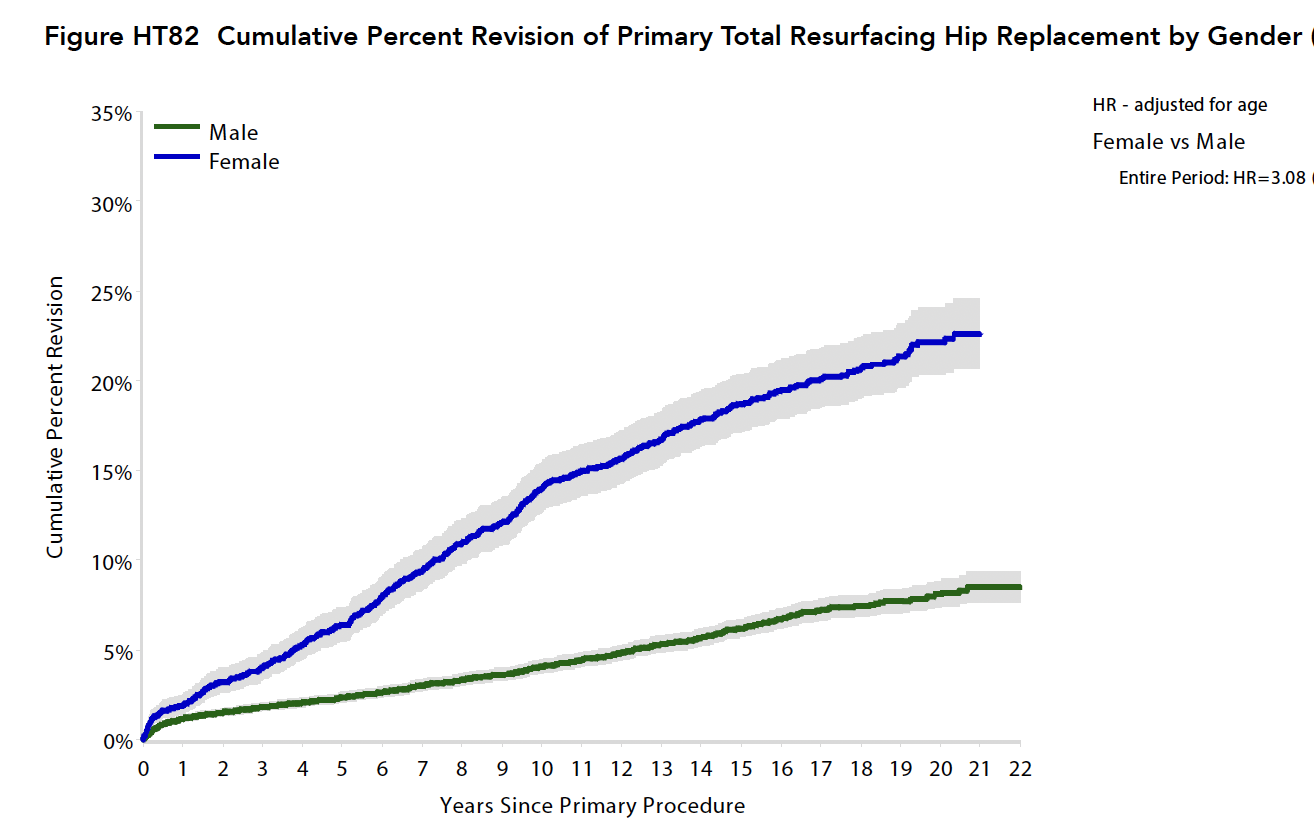

Australian Joint Registry 2023

20 year revision rate 20,000 hip resurfacing

- resurfacing 11%

- conventional THA 8%

In 2022

- resurfacing was 80% less common than in 2005 / 0.7% of all THA

- 97.5% performed in males

| Diagnosis | 20 year revision % |

|---|---|

| OA | 11 |

| DDH | 19 |

| AVN | 16 |

| Prosthesis | 15 year revision % |

|---|---|

| Adept | 6.5 |

| Birmingham | 9.5 |

| Head size mm | 20 year revision % |

|---|---|

| < 45 | 31 |

| 45-49 | 15 |

| 50-54 | 8 |

| > 55 | 6 |

| Male | Female | |

|---|---|---|

| 5 year | 2.3 | 6.4 |

| 10 year | 4.1 | 14 |

| 15 year | 6.2 | 18.7 |

| 20 year | 8.1 | 22.1 |